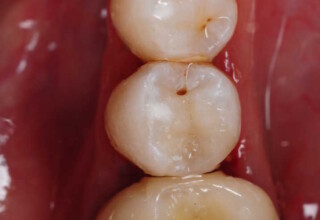

Αποκατάσταση Οπίσθιου Απονευρωμένου Δοντιού με Ανασύσταση Σύνθετης Ρητίνης

Η συνήθης αποκατάσταση ενός απονευρωμένου οπισθίου δοντιού είναι με μια στεφάνη. Ο κύριος λόγος είναι η προληπτική προστασία από κάταγμα και την επακόλουθη εξαγωγή. Σε πολύ συγκεκριμένες περιπτώσεις όπου εξειδικευμένα κριτήρια (κυρίως η ποσότητα της εναπομείνουσας οδοντικής ουσίας) ικανοποιούνται ή όταν η οικονομική δυνατότητα του ασθενή το επιβάλει, μια εκτεταμένη ανασύσταση συνθέτης ρητίνης μπορεί ν’αποκαταστήσει την αισθητική και λειτουργικότητα του δοντιού.